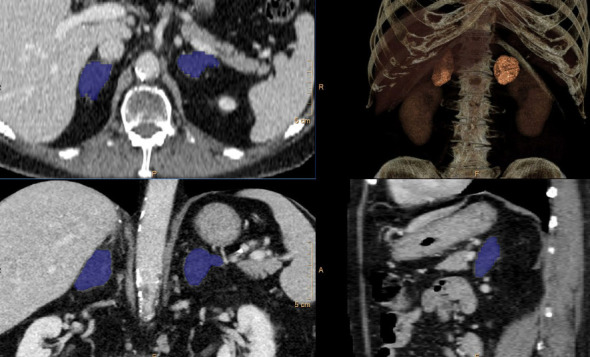

We report a case of successfully lateralized adrenal cortisol hypersecretion by adrenal venous sampling (AVS) and improved by surgery. AVS is a commonly used tool to guide surgical management of primary hyperaldosteronism. It can determine lateralization, leading to unilateral adrenalectomies of the correct side, or nonlateralization, which precludes surgery. The use of AVS in determining lateralization in hypercortisolism is a growing field of discussion. Currently, there is no defined or unanimous protocol behind procedural details and interpretation of results. In this report, we describe the AVS protocol at our institution for hypercortisolism, interpretation of the results, and corresponding surgical outcomes for a case of mild autonomous cortisol secretion.

Abstract Image